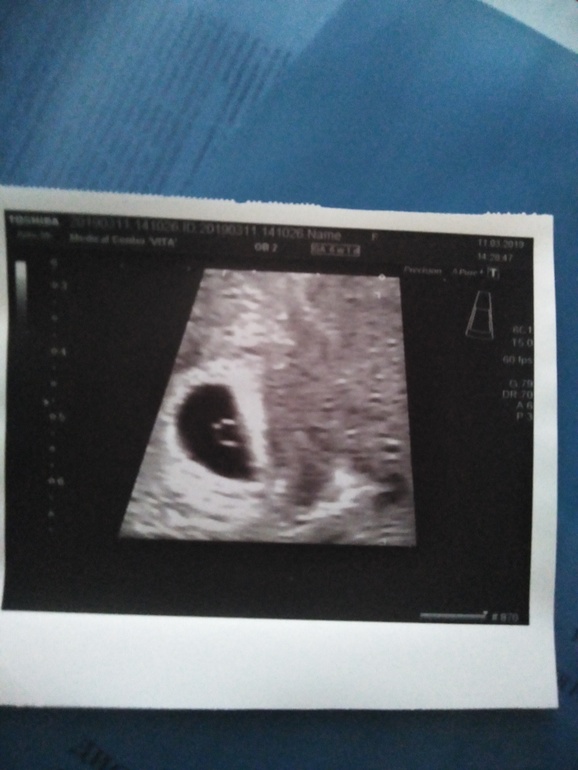

Ну токс не повод думать что опять девочка будет,,,лёгкой беременности,,, А есть фото узи первого 6,7 недель?можно погодать по методу Рамзи кто будет?

это ванинально

это сверху

Будем надеятся что МАЛЬЧИК ,,очень похоже,🙏🙏🙏🙏🙏🙏🙏🙏🙏🙏🙏✊✊✊✊✊✊✊✊✊✊отпишитесь когда будет скрининг,,буду ждать